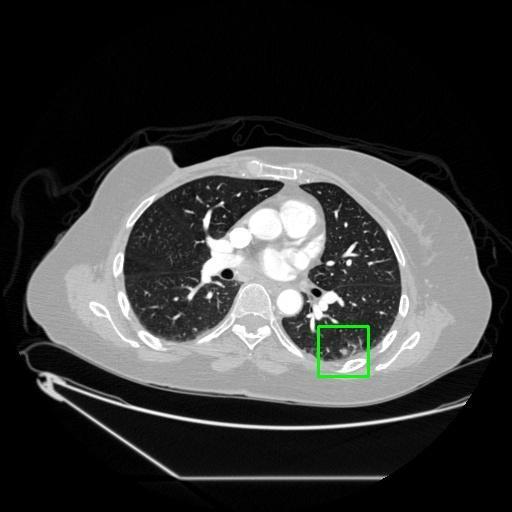

We developed an AI-based system using deep learning models for analyzing lung CT scans to detect and classify pulmonary nodules. We chose the YOLOv11 architecture for its enhanced object detection capability and adapted it specifically for medical imaging, incorporating pixel-level precision and severity classification.

Classification into three severity levels with colored bounding boxes.

Designed a severity classification system that categorizes nodules into null, moderate, and severe using colored bounding boxes, assisting in rapid clinical decision-making.